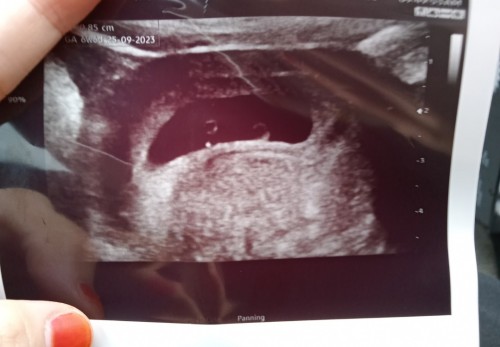

Scan 6weeks 6days

Hi . Nak tanya normal ke ada nmpk dua bulat kat situ ? Doc tak ckp apa apa . Bulat kecik tu ke yolk sac? Alhamdulillah dah ada heartbeat . Ini anak first jd saya kurang tahu .

1 yolk sac, 1 lg amniotic sac

twin ke?

saya pun tak pasti . td dgr stu heartbeat je yg belah kiri tu .